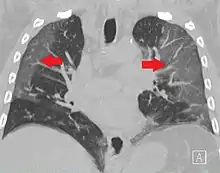

High-resolution CT image showing ground-glass opacities in the periphery of both lungs in a patient with COVID-19 (red arrows). The adjacent normal lung tissue with lower attenuation appears as darker areas.

CT image in patient with COVID-19 showing bilateral ground-glass opacities at the periphery of both lungs.

Ground-glass opacity is among the most common imaging findings in patients with confirmed COVID-19.[16][17] One systematic review found that among patients with COVID-19 and abnormal lung findings on CT, greater than 80% had GGOs, with greater than 50% having mixed GGOs and consolidation.[16] GGOs with mixed consolidation has most often been found in elderly populations.[18] Several studies have described a pattern among initial, intermediate, and hospital discharge imaging findings in the disease course of COVID-19. Most commonly, initial CT imaging reveals bilateral GGOs at the periphery of the lungs. During initial stages, this is most often found in the lower lobes, although involvement of the upper lobes and right middle lobe has also been reported early in the disease course.[16][18] This is in contrast to the two similar coronaviruses, SARS and MERS, which more commonly involve only one lung on initial imaging.[19][20] As the COVID-19 infection progresses, GGOs typically become more diffuse and often progress to consolidation.[11][18] This is sometimes accompanied by the development of a crazy paving pattern and interlobular septal thickening.[18] In many cases the most severe pulmonary CT abnormalities occurred within 2 weeks after symptoms began.[17] At this point, many individuals begin showing resolution of consolidation and GGOs as symptoms improve. However, some patients have worsening symptoms and imaging findings, with further increase in septal thickening, GGOs, and consolidation. These patients may develop lung "white-out" with progression to acute respiratory distress syndrome (ARDS) requiring treatment escalation.[17][21]